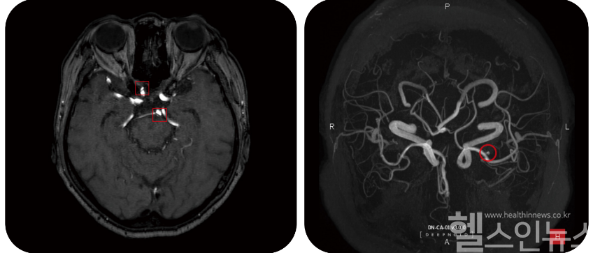

‘메디컬 재팬(Medical Japan)’은 일본의 의료·병원·제약 산업 전시회로, 매년 오사카와 도쿄에서 개최된다. 다양한 의료 전문가와 산업 관계자가 참석하는 이 행사에서 딥노이드는 ‘DEEP:NEURO(딥뉴로)’와 ‘M4CXR’ 모델을 중점적으로 알린다.

M4CXR은 흉부 X-ray에서 병변을 탐지하고, 판독문을 자동으로 작성하는 생성형 AI 모델이다. 판독 결과에 대해 채팅을 통한 질문이 가능하며, 자동판독결과에 대한 상세한 정보를 제공한다. 이는 의료진의 과중한 업무를 줄일 수 있으며, 한층 고도화된 판독 결과를 제시하도록 돕는다.